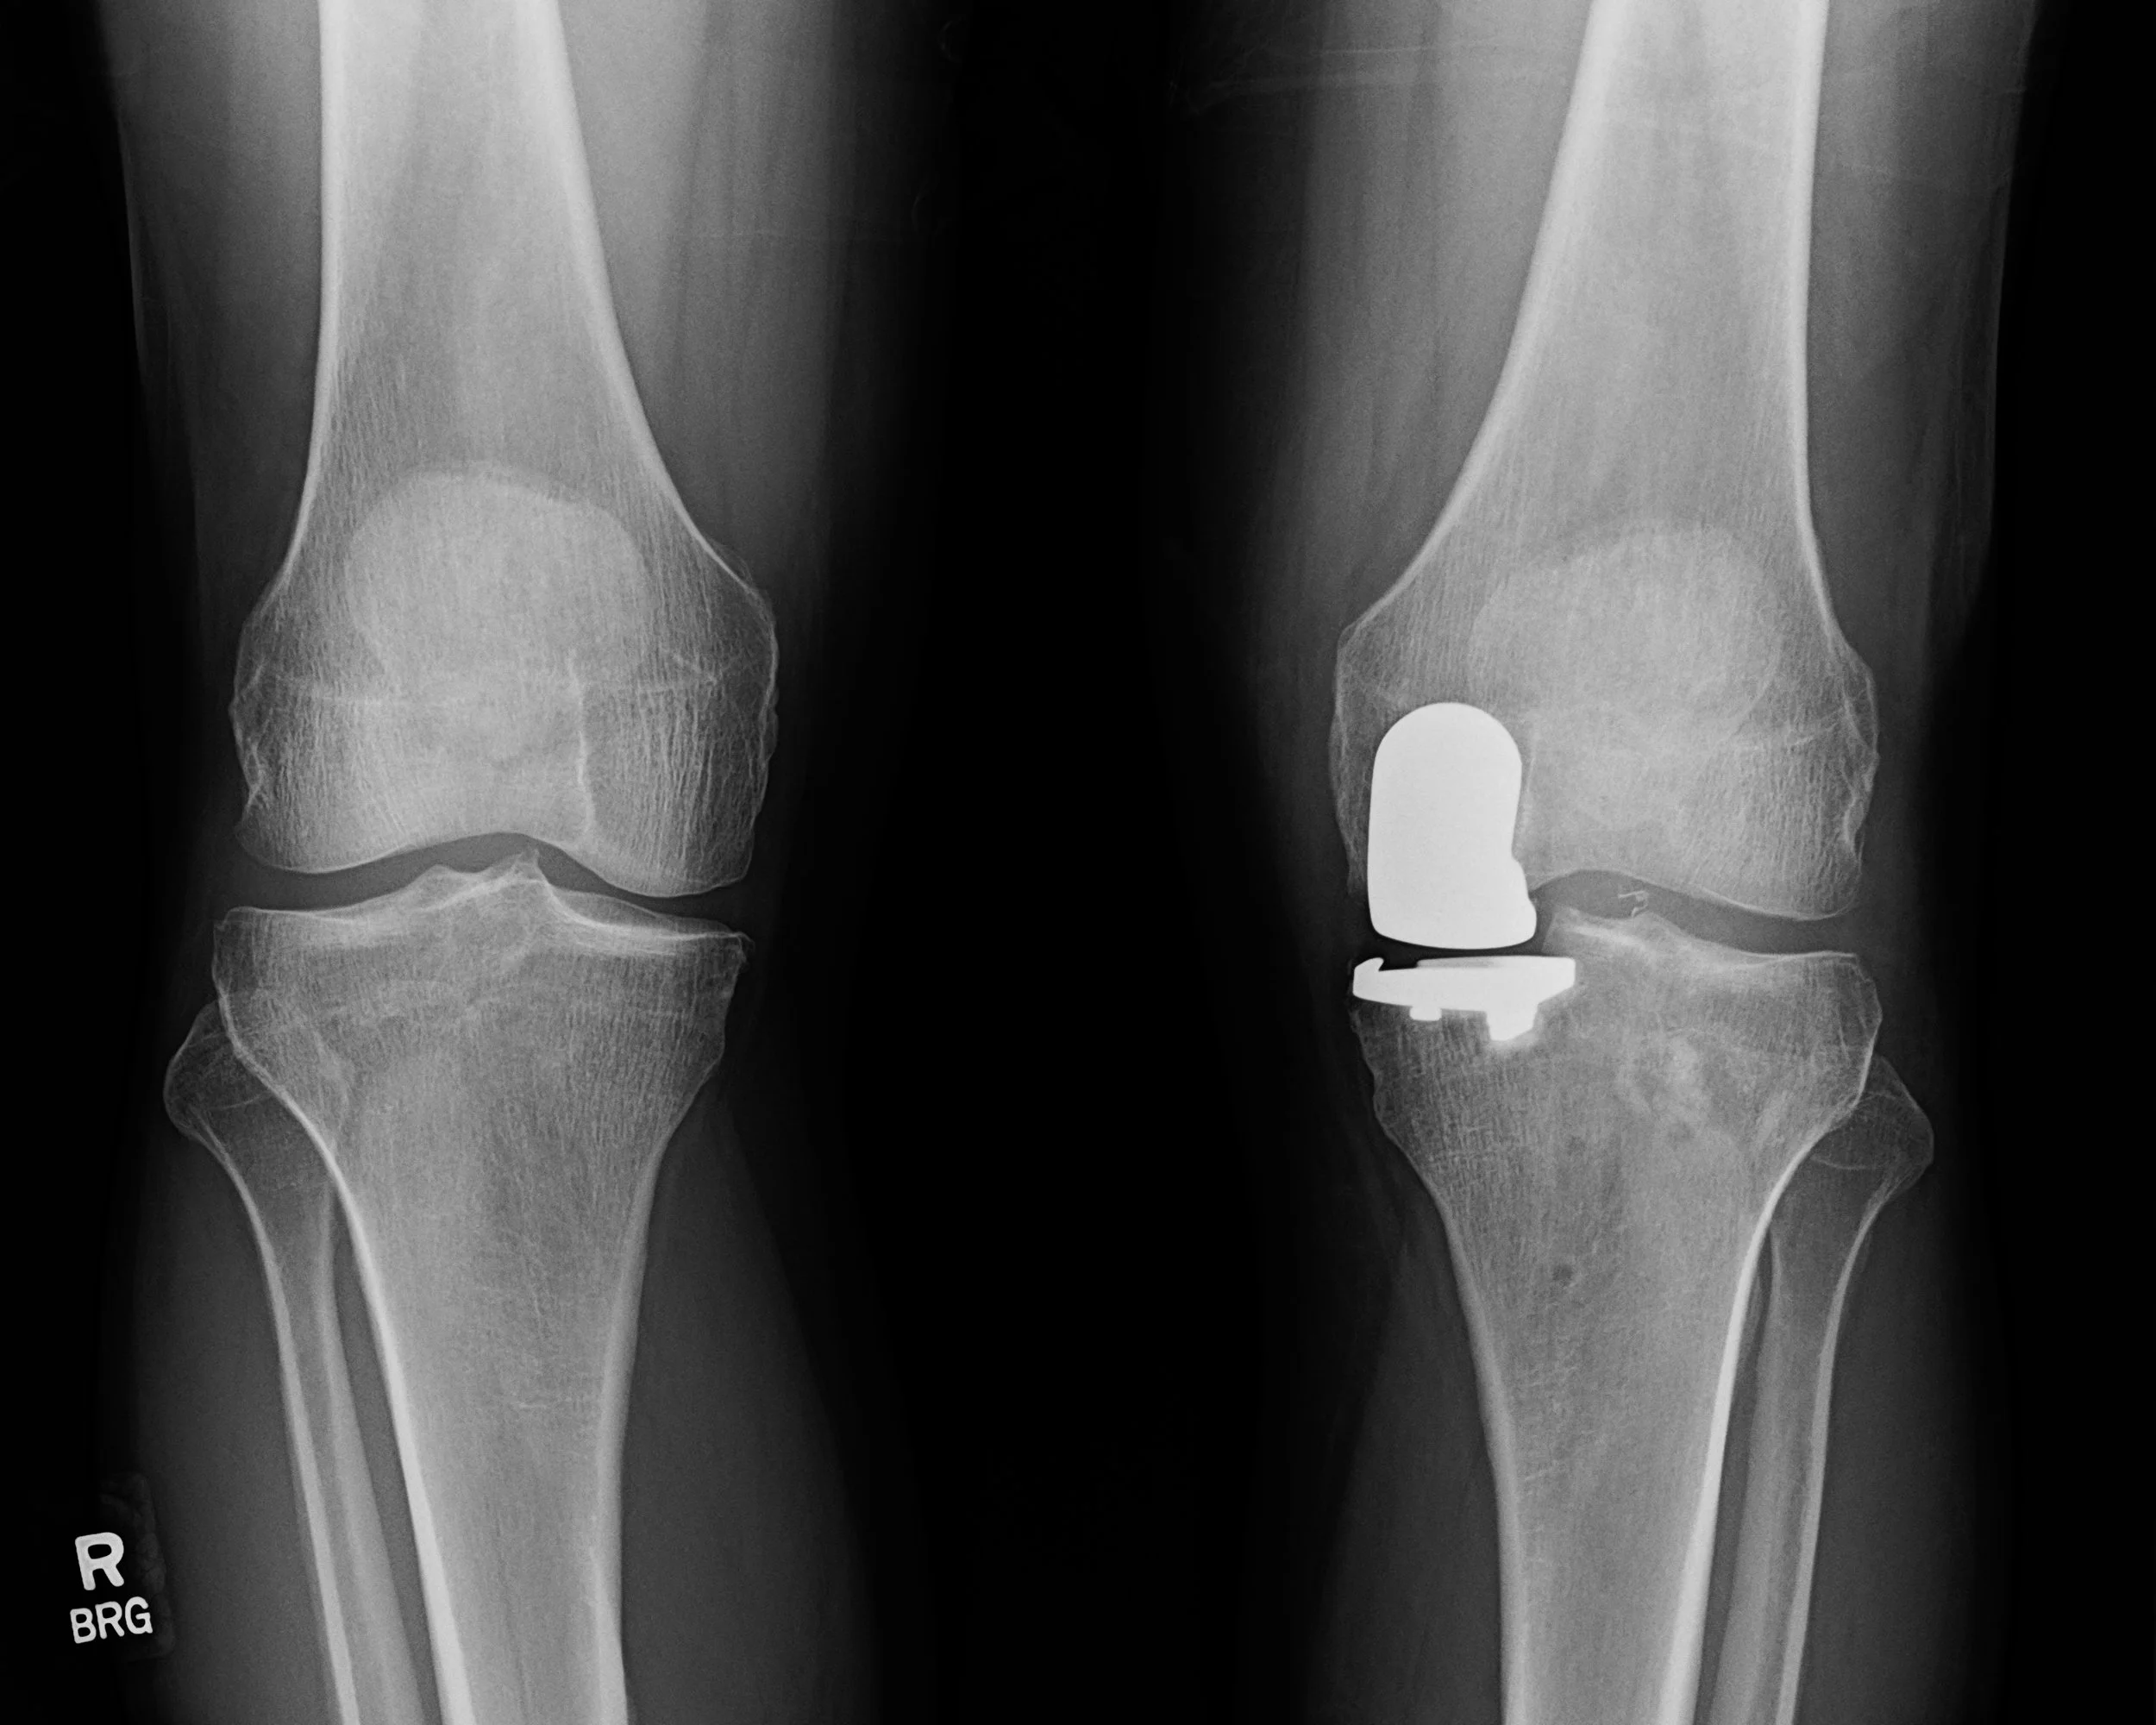

X-ray of both knees showing joint space narrowing from osteoarthritis.

Who Is a Candidate for Partial Knee Replacement?

Patients may be candidates when arthritis is limited to a single compartment of the knee.

• Arthritis confined to one compartment of the knee

• Intact knee ligaments, particularly the ACL

• Normal knee alignment and stability

• Failure of conservative treatments such as medications, injections, and therapy

• Pain localized to one side of the knee

Patients with advanced arthritis affecting multiple compartments of the knee are usually better treated with total knee replacement.